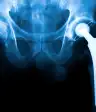

联合替代(关节成形术):如果您对OA的手术,机会是一个关节替代 - 当骨骼的损坏端被移除并用金属或塑料部件替换时,产生缓冲区,使您的骨骼不会一起擦拭。

成功率很高——约90%的患者报告髋关节置换术后10年疼痛减轻,85%的患者在膝关节置换术后10年疼痛仍然减轻。但手术的结果很大程度上取决于你的健康和手术后的健康水平。那些身体非常虚弱或健康状况不佳的人患并发症的风险更大。

虽然髋关节和膝关节置换是最常见的,但几乎任何关节都可以进行置换,包括肩膀、手指关节、脚踝和肘关节。